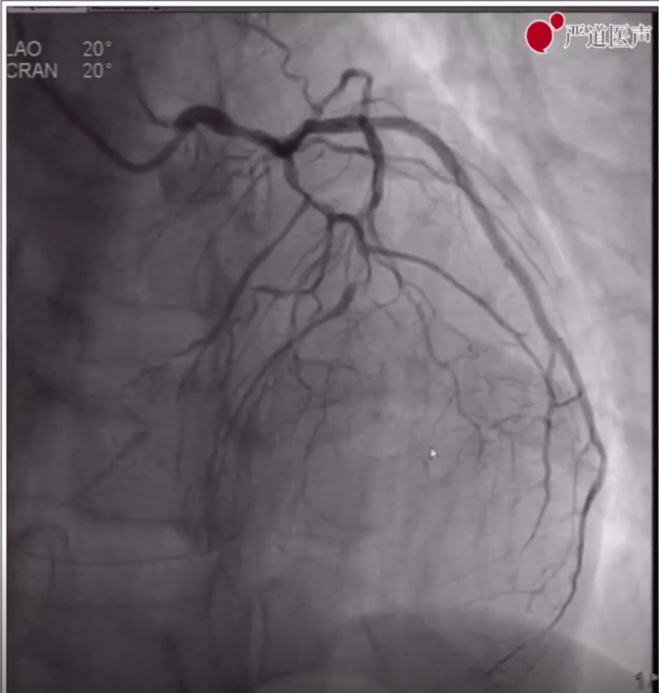

1、术前造影显示LAD弥漫病变、中段完全闭塞,LCX原支架血流通畅,RCA血管纤细、中段完全闭塞,远段侧枝循环形成。

LAD造影图像

RCA造影图像